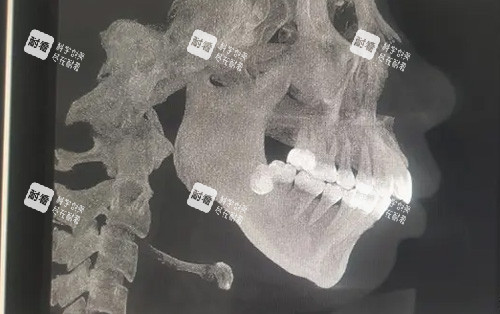

术前准备:患者需要进行多方面的口腔检查、影像学检查(如X光片、CT等),以确定上下颌骨的具体情况和手术方案。同时,还需要进行正畸治疗,为手术创造良好的牙齿排列条件。

手术操作:手术通常在全身麻醉下进行。医生会先在口腔内做切口,然后截断上下颌骨的特定部位,将其移动到预定的位置,并使用钛板、钛钉等固定材料进行固定。手术过程较为复杂,时间较长,一般需要3 - 5个小时。